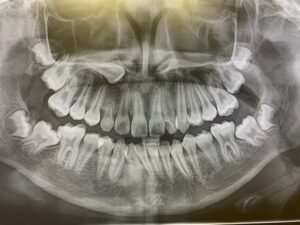

② レントゲン(正面セファロ・側面セファロ・パノラマ)

最近、特に「シュミレーション」と口の中のレントゲン(パノラマ)を使って診断を

してもらった!というお話を伺います。

これはあくまで、診断ではなく、シュミレーションや参考資料になります。